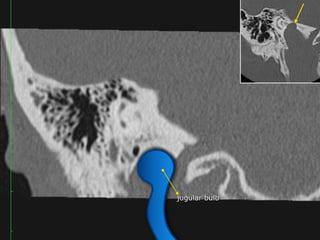

CT Temporal Bone Search Pattern with selected images :

Other structures/landmarks:

•Styloid process

•Stylomastoid foramen

•Petrous apex

•Mastoid air cells

•Sigmoid sinus

•Cochlear promontory

•Carotid canal

•Tegmen

•Jugular bulb